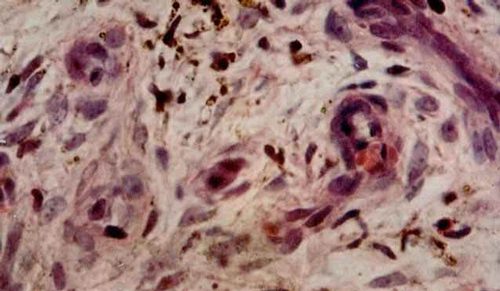

aposis肉瘤皮肤组织活检

图注:aposis肉瘤 皮肤活组织检查 石蜡切片H-E染色 光镜(4×10)(10×10)(10×40)可见肿瘤组织中有许多新形成的血管,血管扩张,内皮细胞肿大突出于管腔内,红细胞外溢,含铁血黄素沉积。肿瘤由成纤维细胞、上皮样细胞淋巴细胞组成,并有大小不等、染色较深的圆形、椭圆形细胞。